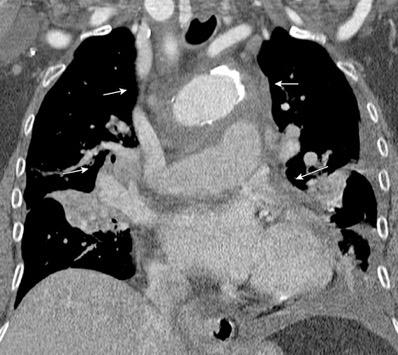

Ganglios retroperitoneales (flechas negras)

germinales del testículo izquierdo Nódulos pulmonares múltiples. (flechas verdes). Ganglios paratraqueales. (flechas amarillas). Dudoso ensanchamiento retrocrural (flechas negras)

Panda A et al. “Straddling Across Boundaries”. Thoracoabdominal Lesions: Spectrum and Pattern Approach. Curr Probl Diagn Radiol, 2015